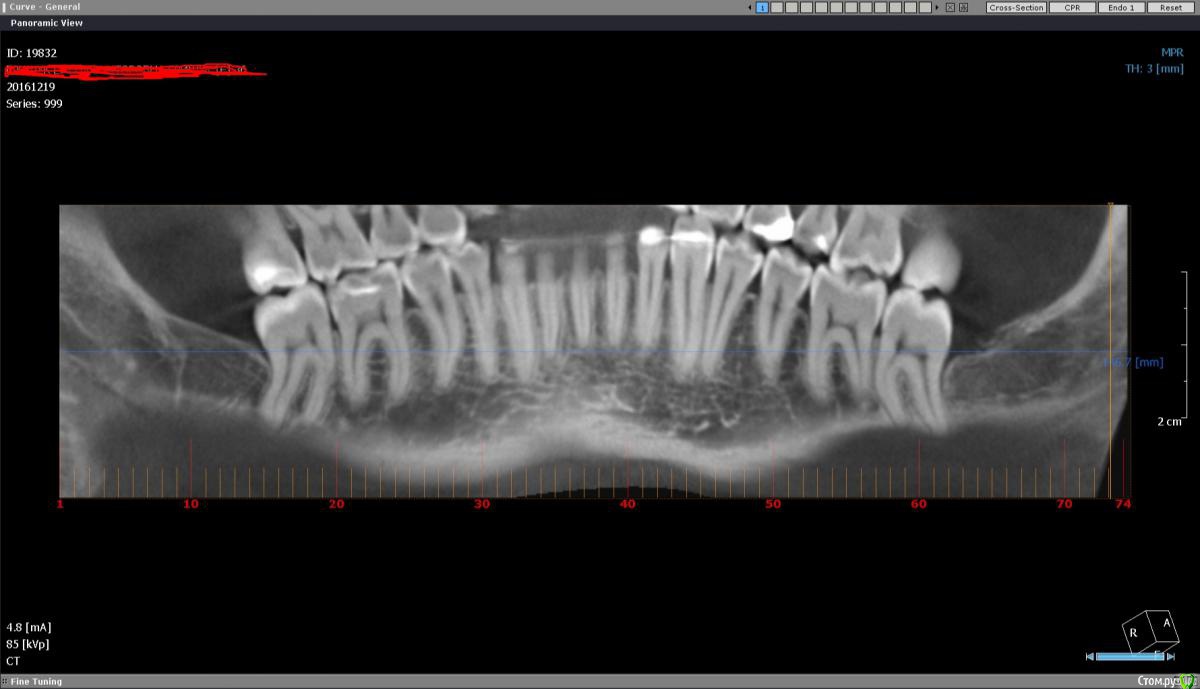

ЕленаR Опубликовано 20 ноября, 2016 Поделиться Опубликовано 20 ноября, 2016 (изменено) Добрый день уважаемые врачи. С момента своей имплантации возвращаюсь и возвращаюсь сюда. По сути: в детстве попала в аварию, две верхних единички выбила. В то время выход был только один-мост на двойки. В 32 года решила установить импланты, и вот мне уже почти 37, а я все лечусь. Врач говорил, что все будет окей, и я согласилась на имплантацию не думая, что будет все так сложно. Про мытарства во время имплантации писать не буду, они были все время. Не один из этапов имплантации не прошел без косяков. Но суть не в этом. Через 1,5 - 2 года импланты были установлены, но при этом шатались двойки! Отчего такое может быть? Сейчас они укрепились, но не так как раньше. Импланты выглядят как зубы лошади. Коронки были установлены очень высоко, терапевт этой же клиники даже как-то спросил кто так установил импланты под самый гребень. Спасает только то, что улыбка у меня закрытая, не десневая. Прошел год, десна над имплантами поднялась. На чистки езжу регулярно, врач сказал ничего страшного потом закроем. Но над одним из имплантов пошло воспаление. Пришлось срочно ехать в клинику. Врач предположил, что воспаление началось из-за того что переохладилась, и из-за того что лезу туда зубной щеткой (а как тогда чистить зубы не представляю) назначили операцию. Операцию делал другой врач, пояснил что у меня тонкий фенотип десны, и они решили нарастить мне лоскут . Лоскут нарастили. И вот прошло три месяца , имплант начал болеть. Болит как настоящий зуб. Пропила антибиотки болеть перестал. В клинику где мне устанавливали импланты я больше ни ногой. Могут ли мне удалить импланты в другой клинике или надо обращаться где ставили? Очень ли это болезненная и травмирующая процедура? Записалась по интернету в две клинике на прием. Ответ пришел, что у меня сложная ситуация будут смотреть. Все это время думала, что это у доктора не хватило опыта мне сделать имплантацию во фронте как положено. Сейчас начинаю сомневаться, что если все так сложно, не возникнет ли повторение ситуации? Может тот доктор сделал все что было в силах в моей ситуации. Задумываюсь о другом виде протезирования. Но двойки у меня стали очень слабые. Если ставить мост и захватить клыки, будет ли такая конструкция устойчива? смогу ли я такими зубами кусать без проблем? Или может быть сделать какой-нибудь протез на замках? Боюсь сделать не правильный шаг и навредить себе еще больше. Проблема не только в эстетике, но еще и в способности откусывать пищу. Когда стоял мост на двойках это было проблемой. Посоветуйте пожалуйста как лучше поступить. Мост с захватом клыков, протез на замках или попытка новой имплантации? Снимок сделан три месяца назад до операции. Изменено 20 ноября, 2016 пользователем ЕленаR Ссылка на комментарий

ЕленаR Опубликовано 21 декабря, 2016 Автор Поделиться Опубликовано 21 декабря, 2016 Добрый день. Уже все сделано и нет пути назад. Но хочется услышать ваше мнение и поделиться продолжением своей эпопеи. На приеме врач сразу отправил на КТ.глядя снимки, предположил, что один имплант не стабилен.Поэтому предыдущие врачи сделали сдвоенную коронку. Также сказал, что противник чтобы подсаживали свой костный блок во фронт. Сколько здесь писала про это, никого не удивляло, что мне блок во фронт подсадили. Вообщем вчера мне удалили два импланта, вытаскивали, как мне показалось с трудом. Врач сказал, что импланты стояли в кости на 2/3 и обросли фиброзной тканью. Мне сразу установили два импланта суперлайн и поставили формирователи. Через два дня будут ставить временные коронки, через 3 месяца постоянные. КТ пока выложить не могу, в наличии только тел. Уважаемые специалисты, как вы думаете такой план лечения имеет место быть? И импланты суперлайн хорошо система, это не миниимпланты? До этого стояли xive. Удивило то, что если имплант был меньше чем на половину в кости, почему его так выбивали.Это нормально? Извините за сумбур. Доктор вроде адекватный, но так страшно попасть не в те руки опять. Ссылка на комментарий